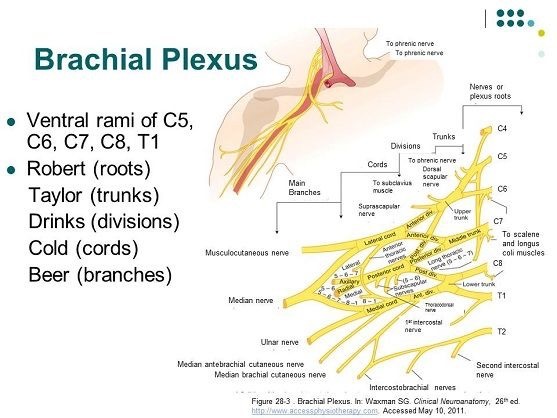

昨年の10月から週に1回のペースでアジャストメントを行ってきました。アジャストメントを行った箇所は、骨盤(腸骨や仙骨)、第6胸椎(T6)から第9胸椎(T9)、第7頚椎(C7)が中心でした。

手指と首・肩・腕の痛みが短期間で劇的に改善しました - 世田谷区岡本

手指と首・肩・腕の痛みが短期間で劇的に改善しました - 世田谷区岡本